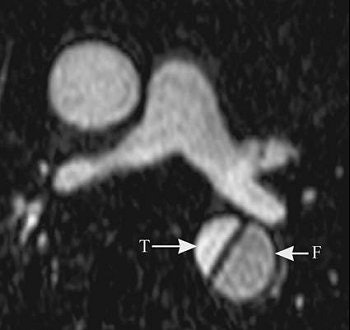

The series of images illustrate the typical manifestations of aortic dissection, including Stanford A (top image, both VR; second image, axial MPR) and Stanford B (third image, arterial phase VR, venous phase VR; fourth image, MIP and VR; fifth image, axial MPR). T = true lumen. F = false lumen. Black arrowhead = entry site. All images courtesy of Qi Liu, Ph.D.

The initial entry site of Stanford B and its relationship with left subclavian artery (top images, both VR).